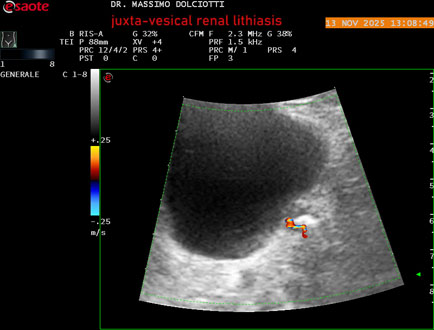

Ecografia del: 13/11/2025

Strumento: Esaote MyLab Eight

Sonda: Convex Multifrequenza 1-8 MHz

Età Paziente: M 59 anni

Motivazione dell'esame: dolori al basso addome ed al fianco sinistro, comparsi la notte precedente.

Commento all'esame: le immagini ed il video documentano al rene sinistro, idronefrosi di 1°-2° grado, con presenza di immagine iperecogena, con cono d'ombra posteriore, allo sbocco dell'uretere sinistro, in sede iuxta-vescicale, delle dimensioni di 6,2 mm, con segno del Twinkling Artifact (o segno di Arlecchino), da ricondurre a litiasi.

Conclusioni: litiasi renale sinistra iuxta-vescicale (left juxta-vesical renal lithiasis).